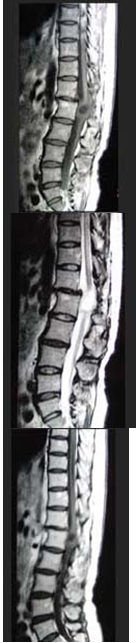

女,34岁,发热,腰部局限性疼痛、活动受限半月余,查体有压痛、叩痛,MRI检查如图,最可能的诊断为()